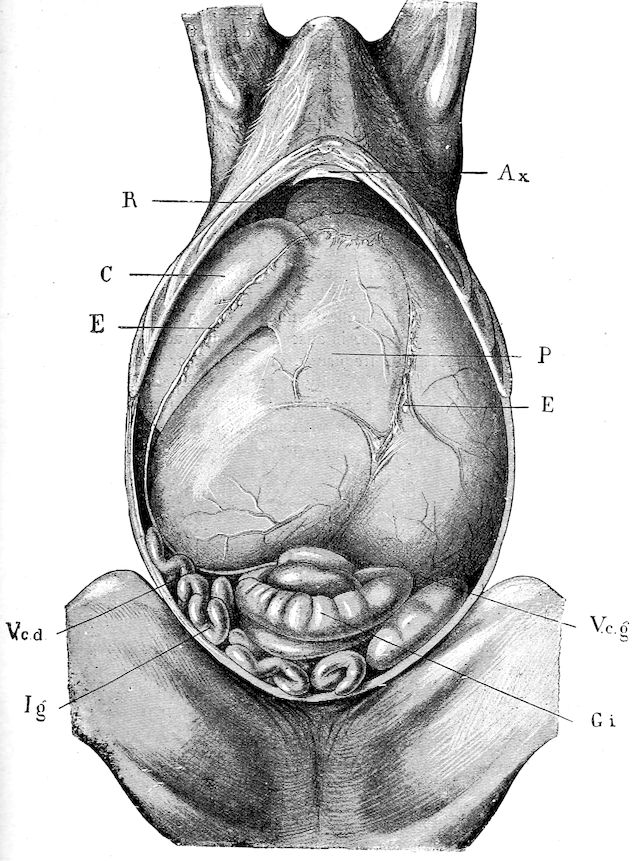

18In the final stages, the bones may be cut with a knife, and a time arrives when bony tissue seems completely to have disappeared; thus, as shown in Fig. 8 herewith, it was possible to cut the entire head of a pig into thin slices without the slightest difficulty. All parts of the head had been affected by the softening change.

From the chemical point of view, the diminution in mineral salts and in phosphate of calcium has long been recognised, but the degree of this change varies according to the phase. In human beings the proportions have been estimated as follows: Normal bone, 50 to 80 per cent. of phosphate of calcium; bone in persons suffering from osteomalacia, 5 to 20 per cent. of phosphate of calcium. The changes in the ossein have not been carefully studied. We only know that histologically the ossein becomes fibrillar, and that chemically it no longer retains its normal composition.